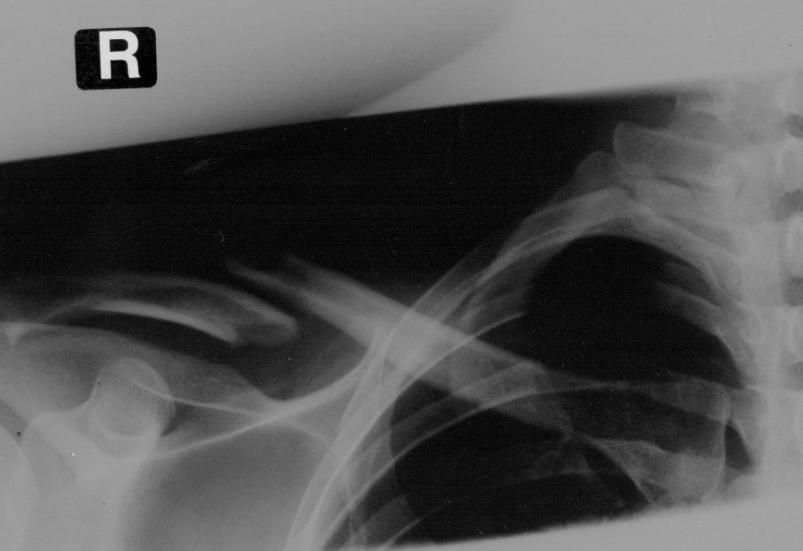

tja mich hats gestern erwischt. Schotter in einer Kurve

Ich hab so einen Kreutzverband bekommen, nun weiss ich nicht wie fest ich den machen sollte. Im Liegen spüre ich den kaum und die Schmerzen halten sich in Grenzen. Wenn ich aber sitze, dauert es keine 10 Miuten und es fängt an übler weh zu tun, wenn ic mich dann wieder lege, knuspelt es lecker in der Schulter und dann wirds wieder besser...